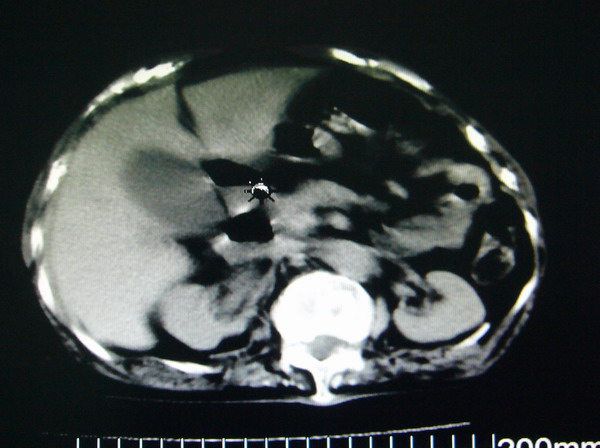

女:83y,转移性右下腹痛2小时,白细胞计数增高。

1.右侧肾盂扩大,肾盏无扩张,考虑:先天性肾盂变异可能性大。

2.胆囊扩张,考虑:胆囊炎。

3.阑尾区域可见以结节样高密度影,结合病史,考虑:阑尾结石,阑尾炎。

右下腹肠系膜增厚,结合病史支持阑尾炎.

右侧壶腹型肾盂可能,建议输路造影或增强

1.右侧肾盂扩大,考虑先天性肾盂变异或肾盂旁囊肿。

2.胆囊扩张,考虑胆囊炎。

3.阑尾区域可见结节样高密度影,结合病史考虑:阑尾结石、阑尾炎。